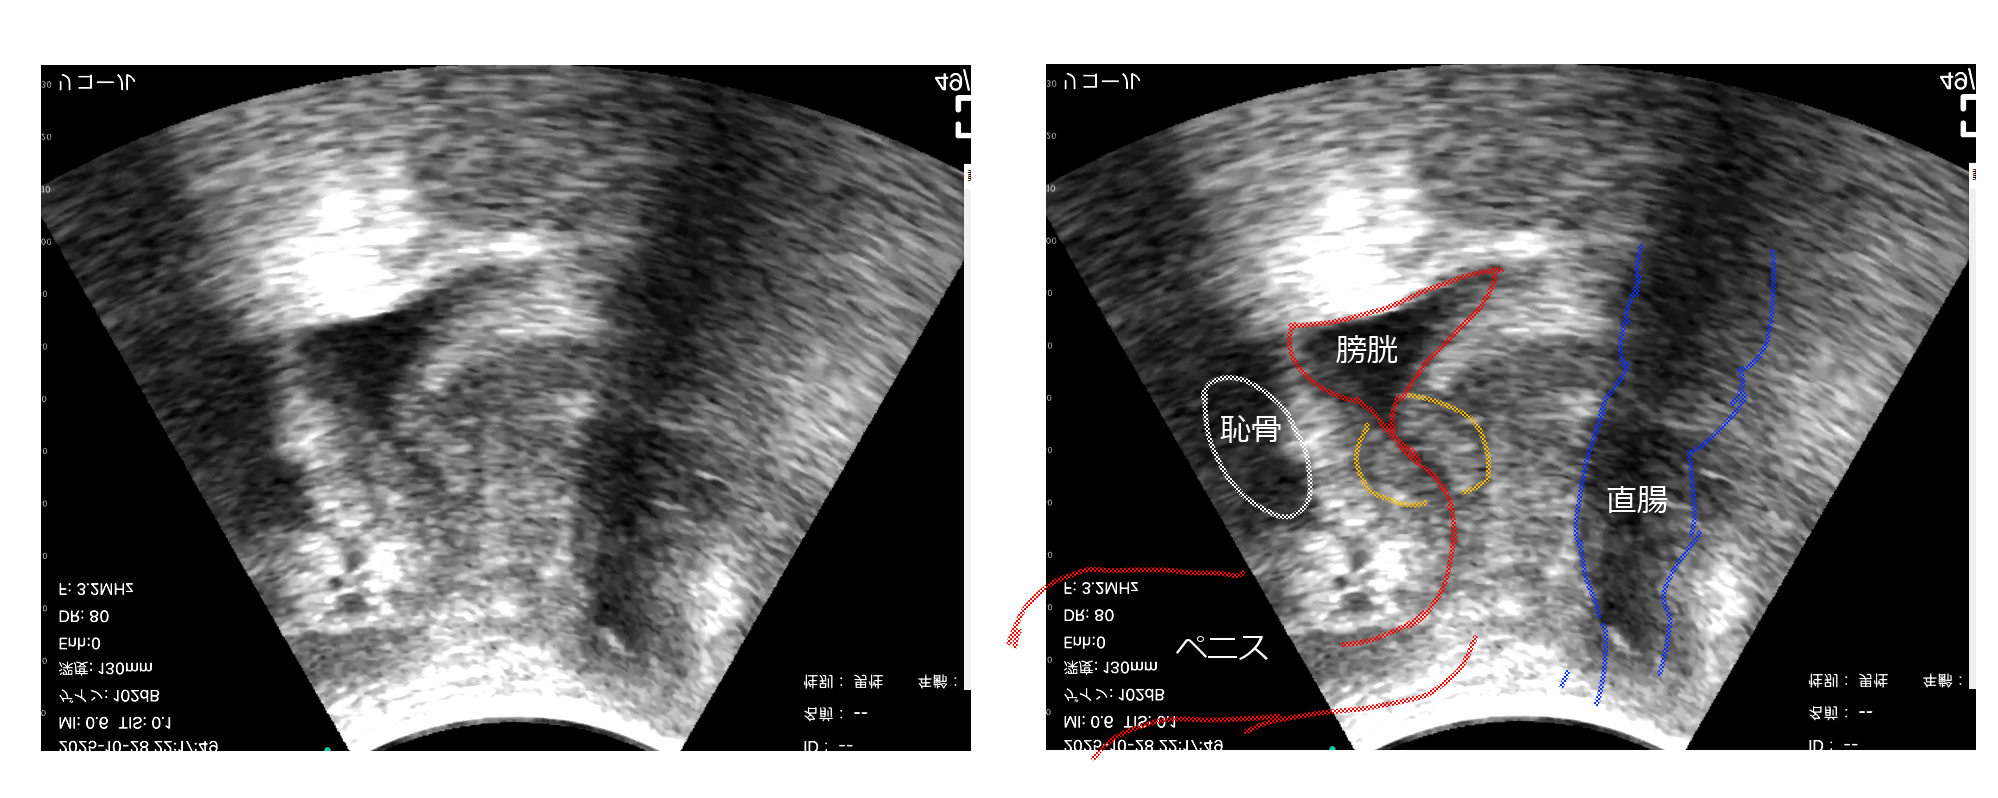

位置関係はこういう形です。だいたい前立腺の位置を把握できました。

左向きの体を横から見た図です。左の黒い塊が恥骨側で、右の黒い塊が直腸です

左が恥骨で右が直腸、直腸の中に固い物体らしい白い部分があります。